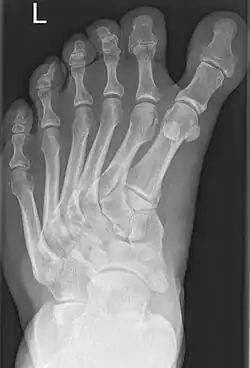

Polymetatarsia is a rare congenital malformation which is characterized by the presence of 6 or more metatarsal bones in the same foot. It is most commonly seen alongside polydactyly,[1] and it often appears between the fourth and fifth metatarsals or beside the fifth metatarsal.